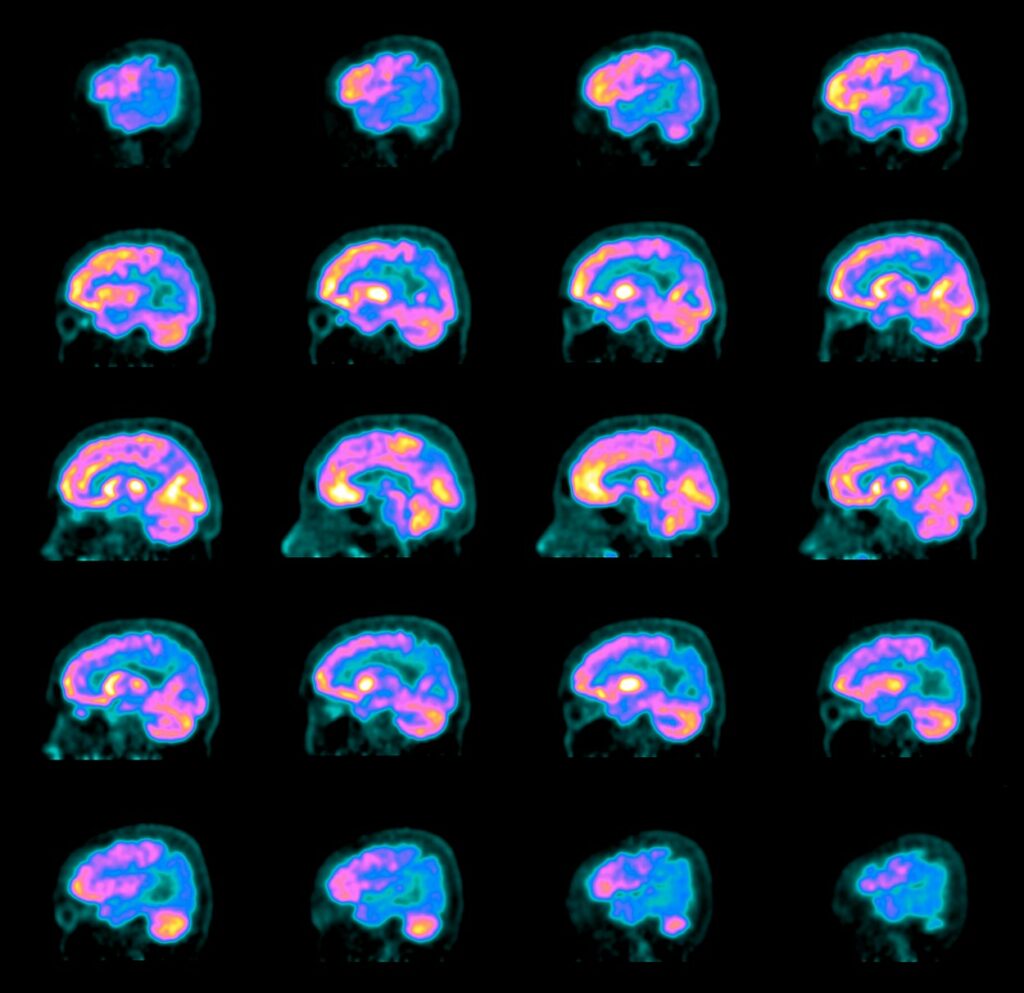

Različne nevrodegenerativne bolezni prizadenejo različne predele možganov. V zadnjih letih je tehnologija slikanja možganov zelo napredovala. Tako lahko zdravniki s pomočjo metod, kakršni sta funkcijska magnetna resonanca (MRI) in pozitronska emisijska tomografija z radioaktivno 18F-fluordeoksiglukozo (FDG PET), pri bolniku prepoznajo za neko bolezen značilen "možganski zemljevid". Nenormalnosti možganskega omrežja je pogosto mogoče prepoznati celo že pred pojavom simptomov, podatke pa uporabiti najprej za diagnosticiranje in nato za spremljanje napredovanja bolezni.

Pri slikanju FDG PET bolniku v veno vbrizgajo radioaktivno označeno glukozo, ki se razporedi po presnovno aktivnih organih. Velik del je privzamejo možgani. Radioaktivni elementi pri razpadu oddajajo sevanje, ki ga zaznajo s posebno kamero PET, in tako zdravniki ocenijo, kateri predeli možganov so bolj, kateri pa manj aktivni. Pri zdravem človeku je razporeditev radioaktivne glukoze enakomerna v celotni možganski skorji in globokih možganskih jedrih. Pri bolnikih z nevrodegenerativnimi boleznimi pa je razporeditev glukoze specifično spremenjena. Z osnovnim pregledom slik FDG PET lahko prepoznajo predele s spremenjeno aktivnostjo, z naprednimi analitičnimi modeli pa lahko ocenijo, kako so ti predeli združeni v omrežja.

Funkcijske slikovne preiskave možganov, ki sta jih opisala slovenska znanstvenika, tudi zgoraj omenjeno slikanje FDG PET, že uporabljajo za diagnostiko nevrodegenerativnih bolezni v večjih bolnišnicah. Med njimi je UKC Ljubljana. "Napredni multivariatni algoritmi, ki jih s kolegom opisujeva v članku, pa so bili do nedavnega rezervirani predvsem za raziskovalno okolje," pojasnjuje Rus. Ker raziskave kažejo, da je metoda zanesljiva, nameravajo omenjene algoritme v kratkem vpeljati v vsakodnevno klinično prakso. Tudi slovenski bolniki bodo imeli tako kmalu možnost na ta način dobiti bistveno natančnejšo diagnozo.